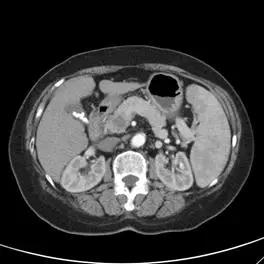

附圖中,最可能為肝臟電腦斷層動態攝影影像之那一相(phase)?

肝臟多相式電腦斷層掃描(Multiphasic CT of the liver)是評估肝臟病灶(如肝細胞癌 Hepatocellular carcinoma, HCC、血管瘤 Hemangioma 等)的標準影像檢查。透過在靜脈注射對比劑(Contrast media)後的不同時間點進行掃描,可觀察血流動力學的變化,進而區分不同組織與病灶的特性。常見的相(phase)包含:無對比劑相(Pre-contrast phase)、動脈相(Arterial phase)、門靜脈相(Portal venous phase)以及延遲相(Delayed phase)。

觀察本題提供的腹部 CT 橫斷面影像,可發現以下關鍵特徵:

- 主動脈(Aorta):呈現極高訊號(極度明亮),顯示對比劑正處於動脈高峰期。

- 下腔靜脈(Inferior vena cava, IVC):呈現低訊號(偏暗),顯示對比劑尚未大量回流至全身靜脈系統。

- 脾臟(Spleen):呈現斑駁狀、不均勻的強化(Mottled enhancement 或稱為 Tiger stripe appearance),這是脾臟在動脈相極為典型的特徵。

- 腎臟(Kidneys):可見明顯的皮質-髓質差異(Corticomedullary different